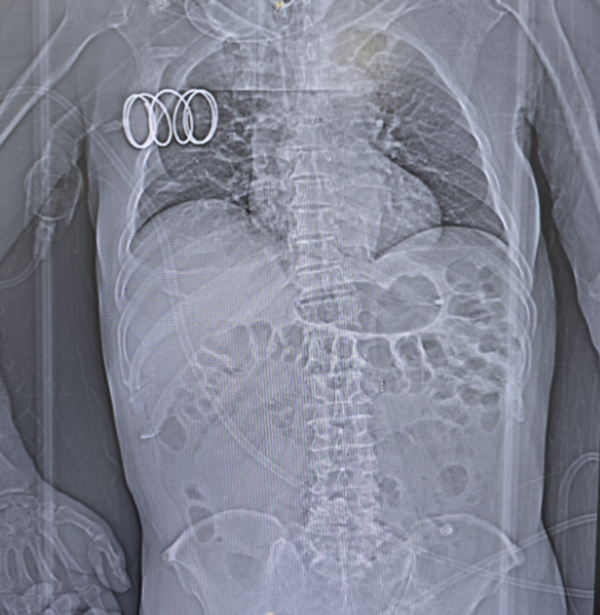

消化科副主任医师李涛副凭借丰富的消化介入经验,无需X线引导,将不需异物钳配合的经鼻超细胃镜经患者右侧鼻腔缓缓进入,抵达十二指肠远端。随后,通过活检通道送入导丝至门齿100cm,固定导丝后小心撤出超细胃镜,由助手丰丙程主治医师协助固定导丝,经导丝将肠梗阻导管顺利送达距门齿 90cm 处。为确保导管位置准确且功能正常,再经左侧鼻腔进超细胃镜至前球囊处,在直视下注入纯净水15ml观察到导管前端球囊扩张。随后撤镜、撤出导丝,局部体外固定导管。

手术过程十分顺利,仅10余分钟完成操作。术后可见肠液自肠梗阻导管引出,患者无明显不适及抗拒表现。患者肠梗阻症状得到了有效缓解,肠道功能恢复良好,顺利出院。